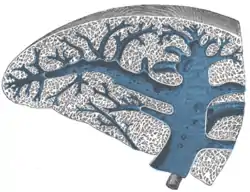

Cross-section of the spleen, showing the splenic vein and its tributaries.

Cross-section of the spleen, showing the splenic vein and its tributaries.